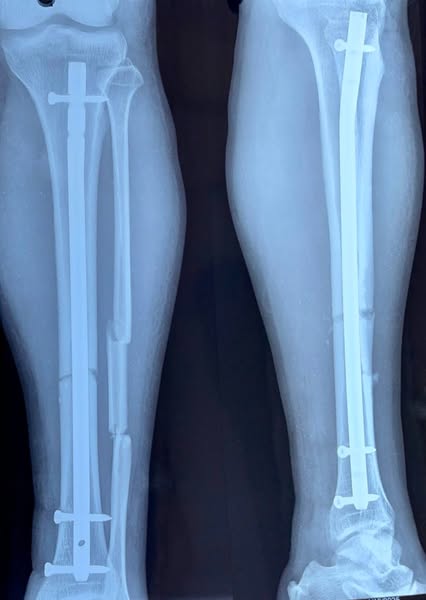

Intramedullary Interlocking Nail for Fracture Fixation

32yr old patient with Alleged history of Road Traffic Accident came with Displaced fracture of Both Bone of leg. Patient was Operated on same day after proper Evaluation. Fracture was Fixed with Intramedullary Interlocking Nail. Surgery was uneventful, post operative recovery was good.

Patient is walking comfortably as of now.